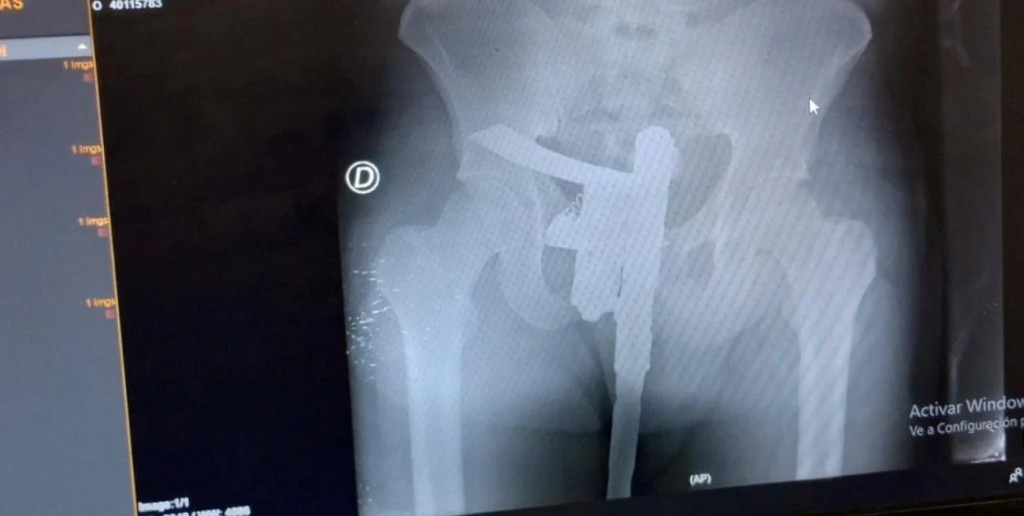

Radiografía con sorpresa: buscaban una fractura y encontraron un arma de fuego

Como es de rutina un médico hizo una primera evaluación y, como el paciente manifestaba dolor en la zona de la cadera, se ordenó realizar una placa radiográfica.

El estudio se concretó de manera normal, aunque minutos después el revelado permitió descubrir una "sorpresa". En la placa se observó que el paciente tenía un arma de fuego oculta entre sus genitales.